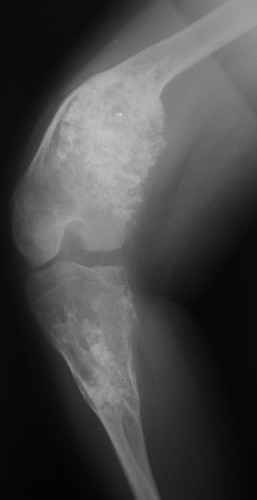

Диагноз: Дисхондроплазия. Варусная деформация дистального метафиза правой бедренной кости; состояние после оперативных вмешательств (1993 и1994 гг.).

Деформация правой нижней конечности с 6 месяцев (стала прогрессировать после года, с момента начала ходьбы). Поставлен диагноз болезнь Олье, варусная деформация, укорочение правой нижней конечности на 4,5 см. 1993 г. - операция остеоклазия на уровне очагов поражения в н/3 правой бедренной кости и в/3 правой большеберцовой кости с одномоментной коррекцией деформации и фиксацией костных фрагментов спицами Киршнера.После начала статической нагрузки (1994 г.) появился рецидив деформации и укорочения. Вторая операция - ЧКО АВФ, аппарат демонтирован через 2недели в связи с развившимся на уровне стержня переломом, после чего находилась в гипсовой повязке до консолидации костных фрагментов. Далеелечилась консервативно в гипсовой повязке. Выраженная деформация и укорочение правой нижней конечности. Относительная длина бедер: справа -34 см, слева - 51 см; анатомическая длина голеней: справа - 29 см, слева - 39 см. Величина варусной деформации на уровне дистального отдела правого бедра составляет - 80 град. Амплитуда движений в коленных суставах (разгибание/сгибание ): справа - 0/0/100 град.; слева - 0/0/30 град. Отмечается боковая и ротационная нестабильность на уровне правого коленного сустава. Амплитуда движений в голеностопных суставах - в норме. Тактика лечения? Заранее благодарю! С уважением,А.В.Владзимирский